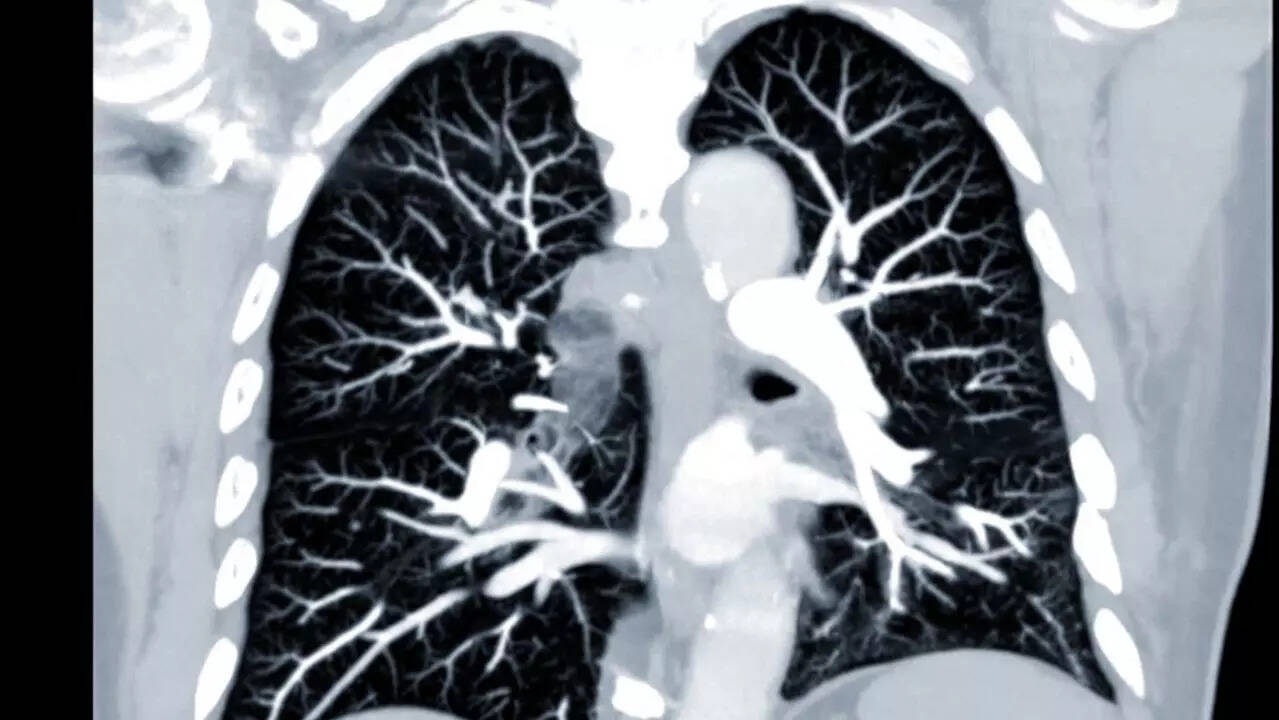

What is bronchial spasm?Bronchial spasms are uncomfortable, frightening, and can make breathing extremely difficult for the person suffering from it. A bronchospasm happens when the muscles surrounding the airways known as the bronchi, which connect the windpipe to the lungs, suddenly tighten. This causes the airways to narrow, restricting the flow of oxygen into the lungs and making it harder to breathe. This also results in wheezing, coughing, and other symptoms.